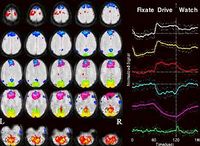

هناك فريق من العلماء حاول الدخول إلى دماغ الإنسان ومعرفة ما يجري أثناء الكذب، واستخدم من أجل ذلك جهاز المسح المغنطيسي الوظيفي fMRI وهو جهاز يعمل بالموجات المغنطيسية ويستطيع كشف نشاط الدماغ.

وبعد العديد من التجارب وجد العلماء أن الإنسان عندما يكذب فإن المنطقة الأمامية من دماغه تنشط بشكل مفاجئ، ولذلك استطاعوا كشف الكذب بواسطة هذا الجهاز ومن خلال تصوير النشاط الدماغي في هذه المنطقة.

يبين جهاز المسح المغنطيسي الوظيفي أن هناك مناطق رئيسية في الدماغ تنشط أثناء الكذب وهذه المناطق هي المنطقة ما قبل الأمامية والمنطقة الأمامية وما تحت القشرة الدماغية.